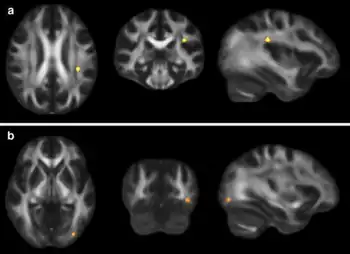

| Increased diffusion on MRI is associated with the severity of post-concussive symptoms | |